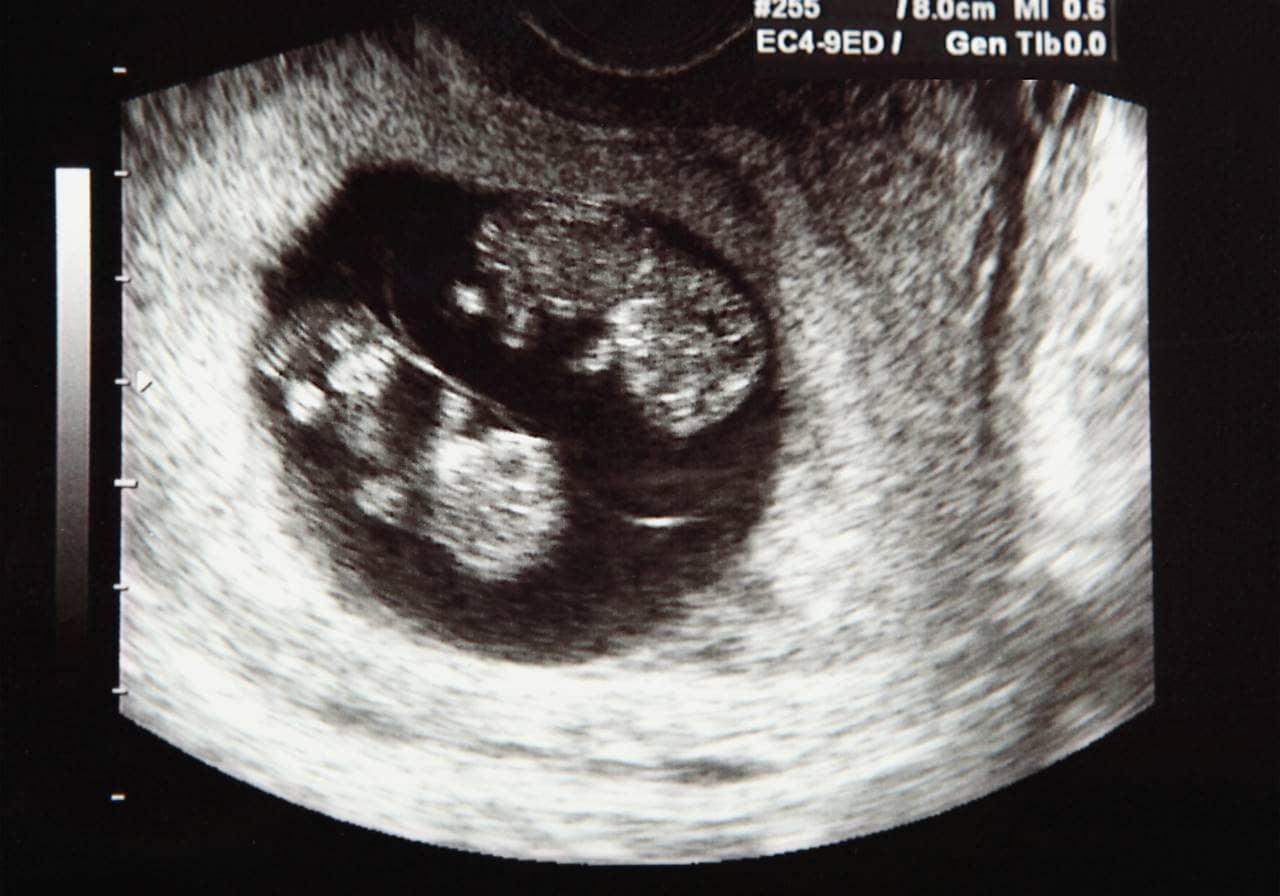

A cerclagem do colo uterino é um procedimento cirúrgico feito para diminuir o risco de parto prematuro, realizado para evitar a abertura antecipada do colo do útero durante a gravidez. Essa técnica pode ser realizada tanto antes quanto durante a gestação, embora seja mais frequentemente indicada para mulheres grávidas.

O procedimento envolve a aplicação de uma sutura ao redor do colo do útero pelo médico, reforçando-o para impedir que se abra antes do momento apropriado.

A cerclagem é geralmente realizada no segundo trimestre da gestação. A partir da 13ª semana de gravidez, quando o risco de aborto espontâneo inicial já reduziu. O tipo de anestesia utilizada — geral, local ou regional — será escolhido de acordo com as necessidades de cada caso.